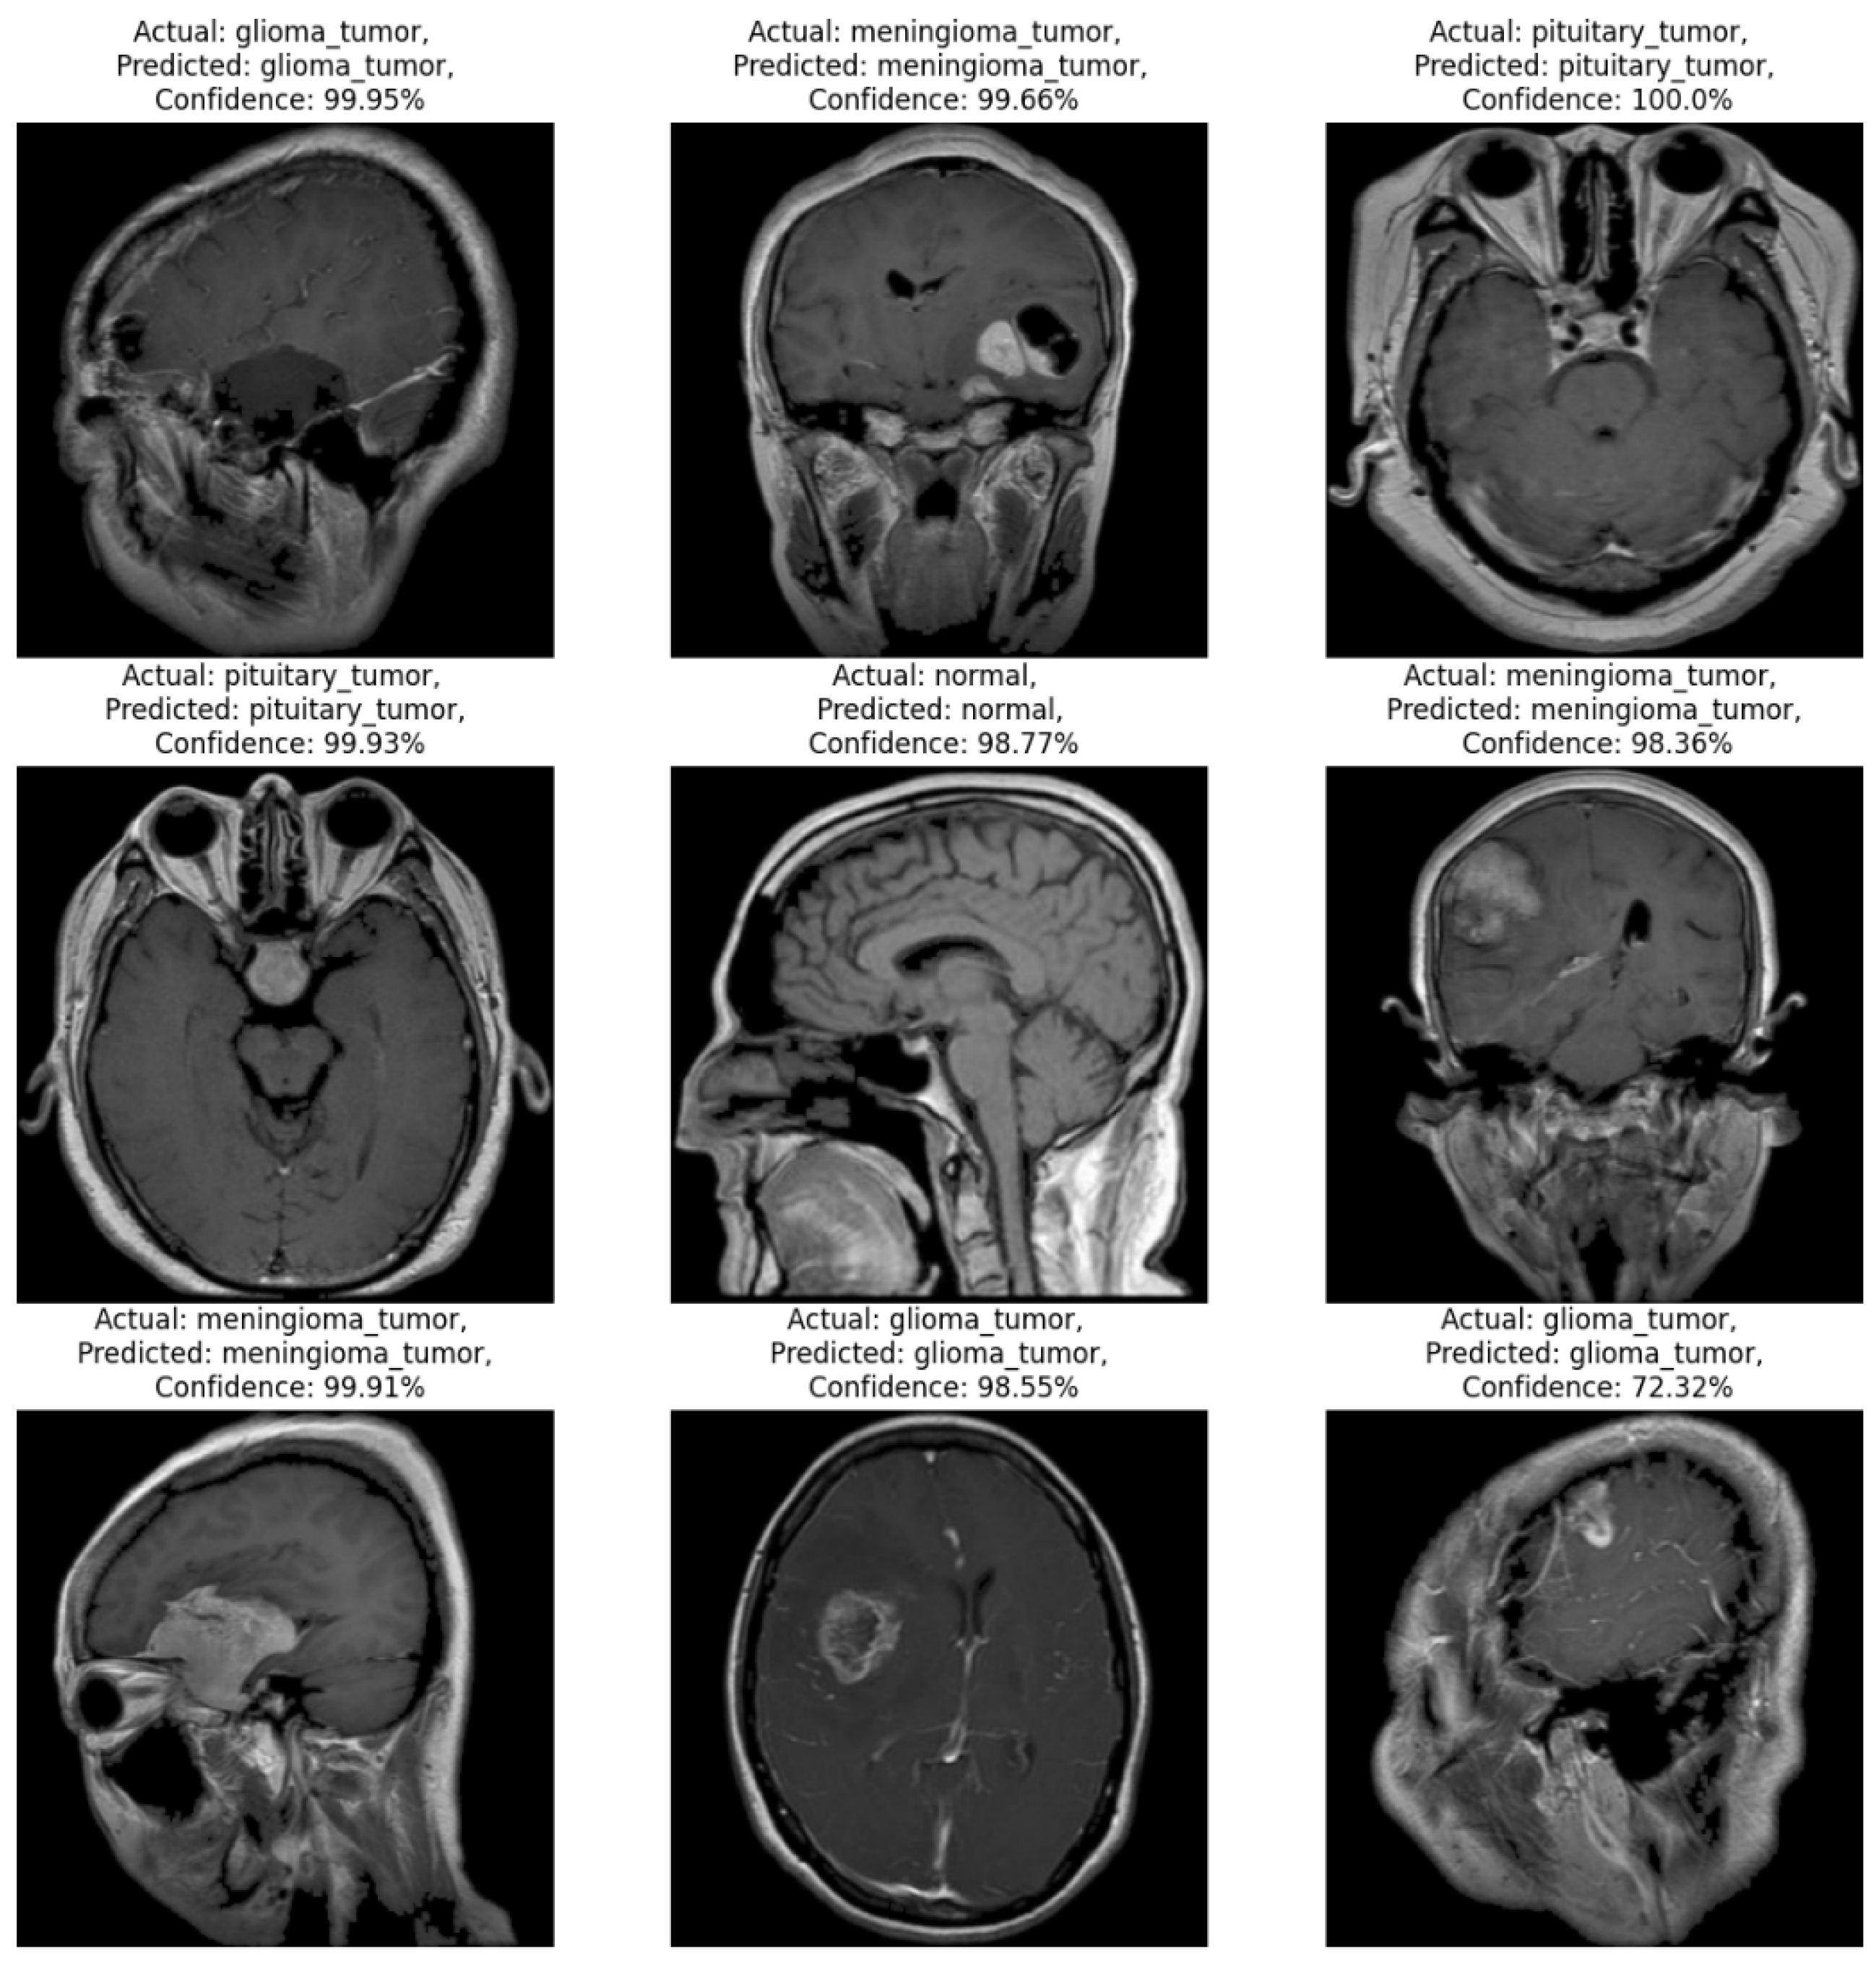

Figure 5. Example MRI predictions: Actual vs. predicted tumor types with model confidence levels.

The displayed output consists of nine MRI images, each annotated with the actual class label, the predicted class label, and the model’s confidence in that prediction. This layout provides insight into the CNN model's ability to classify various types of brain conditions and normal tissue. In most instances, the model's predictions are highly accurate, as indicated by the high confidence levels, often exceeding 98%. For instance, in the first row, images of glioma tumor, meningioma tumor, and pituitary tumor are correctly classified with confidence scores around or above 99%, demonstrating the model's robust differentiation between these tumor types. This high accuracy suggests that the model has effectively learned distinguishing features specific to each category, allowing it to make reliable predictions when presented with images like those in its training set. In the second row, two of the three images are also accurately classified, with confidence levels near 99% for both pituitary tumor and normal tissue predictions. The middle image in this row shows an example of meningioma tumor predicted with a confidence of 98.36%. This slight drop in confidence may indicate a lower certainty in identifying specific features within this image, though the model's overall performance remains strong. The third row further reinforces the model's accuracy. Both glioma and meningioma tumors are accurately classified with high confidence levels (above 98%). However, the image on the far right, which represents a glioma tumor, is predicted correctly but with a lower confidence of 72.32%. This lower confidence could suggest that the image has characteristics that might overlap with features of other classes, challenging the model's ability to clearly classify it with the same certainty as others. This case highlights a potential area for improvement, as it suggests that certain glioma images may benefit from additional feature refinement in the training data.